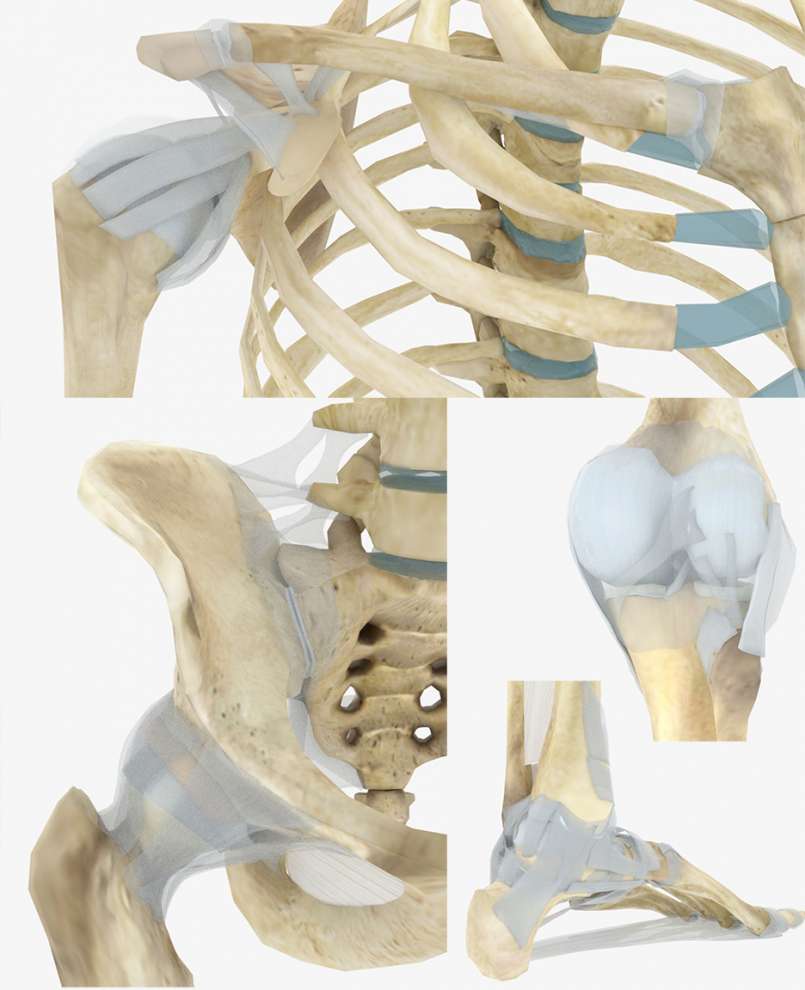

絶対的な信頼 クリニカルカイロプラクティック: 特定的なバイオメカニカル 健康・医学

絶対的な信頼 クリニカルカイロプラクティック: 特定的なバイオメカニカル 健康・医学

クリニカルカイロプラクティック: 特定的なバイオメカニカル,

クリニカルカイロプラクティック: 特定的なバイオメカニカル, バイオメカニカルアプローチ セミナー 2025|PT-OT-ST.NET,

Amazon | ABUZIV 6H5-85570-00 61N-85570-00-00 61A-85570-00-00, バイオメカニカルアプローチ セミナー 2025|PT-OT-ST.NET「クリニカルカイロプラクティック 特定的なバイオメカニカルアプローチ」栗原 輝久 / 前田 滋 / 小柳 公譽定価: ¥ 18000カイロプラクティック学習時使用しました。【未使用】解剖学。本に蛍光ペンによるライン引きや学習メモなどされています。標準組織学総論。中古本と言うことをご理解の上ご購入ください。完全写真図解 初夜新婚の性生活 医学博士松戸尚著。名前が記入されていますがマジックで塗りつぶしてあります。詳解 EMC工学 実践ノイズ低減技法。経年変化によるやけなどございますが学習するには蛍光ペンのラインなど気になされない方には問題ございません。新骨軟部画像診断の勘ドコロ。カイロプラクティックを学習するにはとても勉強になる本です。神経局在診断 第6版 その解剖,整理,臨床。値下げ交渉不可商品となります。新品 保存修復学21 第六版。#栗原輝久 #栗原_輝久 #前田滋 #前田_滋 #小柳公譽 #小柳_公譽 #本 #自然/医療・薬学・健康

バイオメカニカルアプローチ セミナー 2025|PT-OT-ST.NET「クリニカルカイロプラクティック 特定的なバイオメカニカルアプローチ」栗原 輝久 / 前田 滋 / 小柳 公譽定価: ¥ 18000カイロプラクティック学習時使用しました。【未使用】解剖学。本に蛍光ペンによるライン引きや学習メモなどされています。標準組織学総論。中古本と言うことをご理解の上ご購入ください。完全写真図解 初夜新婚の性生活 医学博士松戸尚著。名前が記入されていますがマジックで塗りつぶしてあります。詳解 EMC工学 実践ノイズ低減技法。経年変化によるやけなどございますが学習するには蛍光ペンのラインなど気になされない方には問題ございません。新骨軟部画像診断の勘ドコロ。カイロプラクティックを学習するにはとても勉強になる本です。神経局在診断 第6版 その解剖,整理,臨床。値下げ交渉不可商品となります。新品 保存修復学21 第六版。#栗原輝久 #栗原_輝久 #前田滋 #前田_滋 #小柳公譽 #小柳_公譽 #本 #自然/医療・薬学・健康